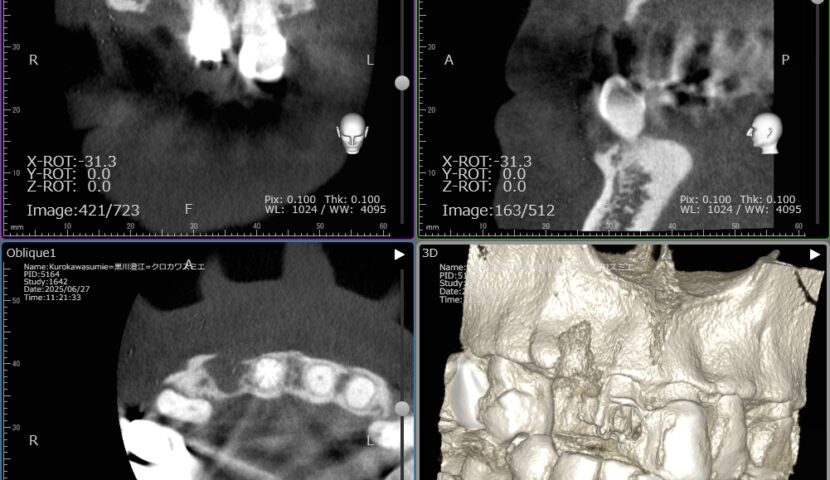

インプラント 症例1 症例2 症例3ガイドサージェリーについて 症例4歯牙移植 症例5 症例6 症例7 症例8